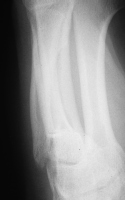

Distal phalanx delayed union with appearance of

probable soft tissue interposition. |

| Unable to achieve

closed reduction. |

| Fracture exposed

through a palmar approach and soft tissue

interposition removed. |

| Reduction and

stabilization. |